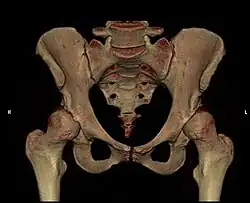

Anatomie des gesunden Beckens (Ansicht von vorne) -

Modell eines gesunden Beckens

Das Becken ist der Mittelpunkt des menschlichen Körpers und vereinigt die Wirbelsäule mit der unteren Extremität (Bein). Gleichzeitig liegen wichtige Organe, wie z. B. die Harnblase, der Enddarm, die Geschlechtsorgane und deren Anhänge, direkt im Beckengewölbe. Große Gefäße und Nerven (Ischiasnerv, Beckenarterie und -vene) gabeln sich hier. Schließlich setzen zahlreiche Muskeln, Sehnen und Bänder am Becken an, die für die Körperstatik und besonders für die komplexen Hüftbewegungen wichtig sind.

Die gewölbeartige Struktur des Beckens und die empfindlichen Weichteilverhältnisse (Nerven, Gefäße, Muskel-Sehnenansätze) machen die Zugangswege kompliziert.